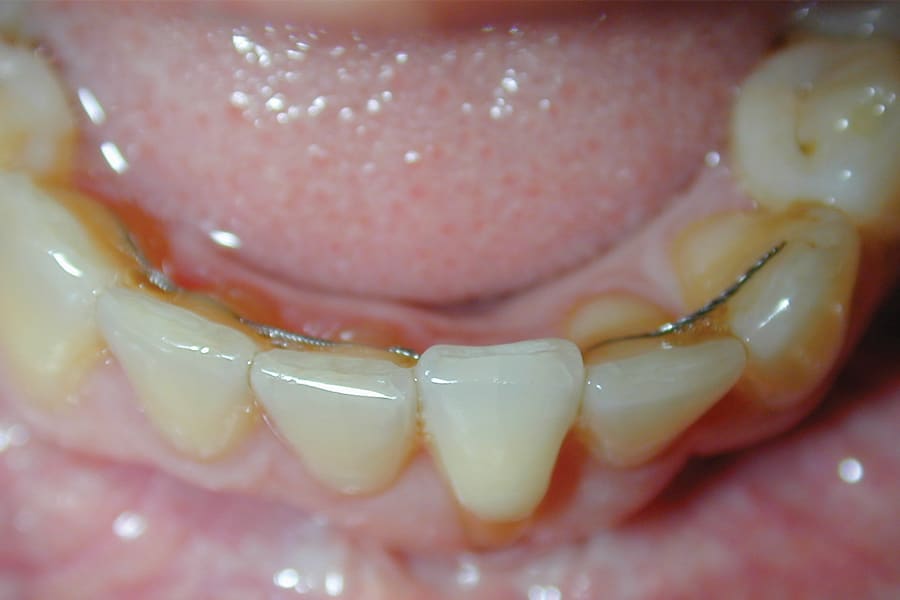

A popular example of this approach is the twisted stainless-steel wire retainer (Figure 1). This design features ease of fabrication and placement as well as minimal cost. Frequently, a twisted lingual retainer can be fabricated chairside and placed immediately with no preparation, impressioning, or laboratory fabrication required. Consequently, this design is commonly utilized. It can be made from a very thin wire (such as a .009" ligature tie) that is folded over and spun down (or twisted) then formed to the arch curvature and direct bonded. Annealing the formed wire prior to placement can be beneficial, as this can remove the "memory" that stainless steel possesses if not permanently deformed.

There are, however, some unfavorable long-term ramifications of this design. Due to the nature of stainless steel, which has memory and over time will partially return to its original shape, these twisted lingual retainers may "unwind" or uncoil and exert unintended forces on the teeth to which they are bonded (Figure 5 and Figure 6, Figure 8 through Figure 11, Figure 14 through Figure 16). This leads to excessive labial or lingual root torquing movements, often resulting in highly undesirable recessions, dehiscences, and fenestrations. Because it may take years for this occurrence to manifest, the orthodontist (who usually places the retainer) is typically both unaware of the situation, as he or she does not customarily follow patients for such long-term periods, and free of blame. The periodontal implications of this outcome can be highly detrimental, as seen in the cases presented herein.